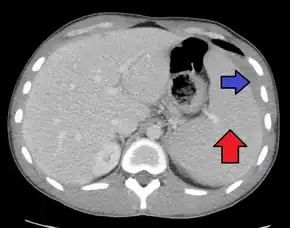

Spleen enlargement is common in the second and third weeks, although this may not be apparent on physical examination. Rarely the spleen may rupture. There may also be some enlargement of the liver.[21] Jaundice occurs only occasionally.[13][23]

Splenomegaly is a common symptom of infectious mononucleosis and health care providers may consider using abdominal ultrasonography to get insight into the enlargement of a person's spleen.[56] However, because spleen size varies greatly, ultrasonography is not a valid technique for assessing spleen enlargement and should not be used in typical circumstances or to make routine decisions about fitness for playing sports.[56]